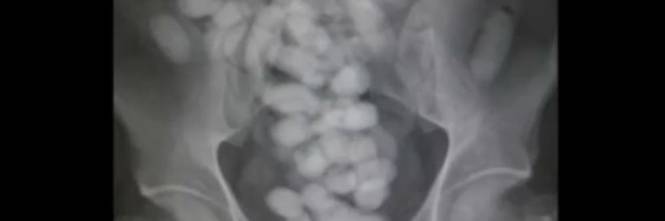

La sostanza stupefacente penalmente rilevante Γ¨ solo quella inserita nelle Tabelle allegate al DPR n . 309/90 . In tal senso si parla pertanto di nozione "legale" di stupefacente . Chiaramente, per accertare la natura psicotropa della sostanza, occorre procedere ad accertamento tecnico di natura chimico-tossicologica .